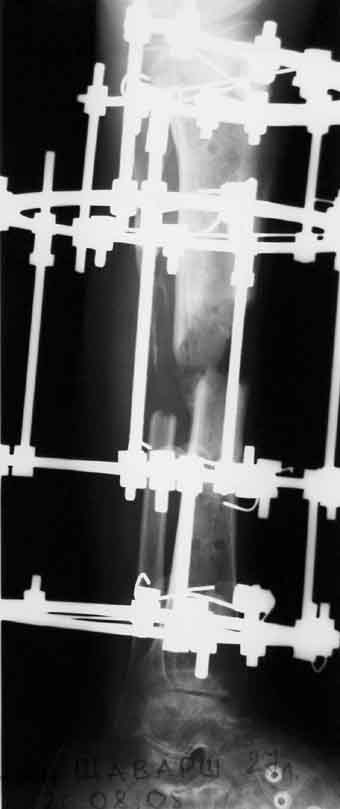

1 июня произведено удаление гвоздя, дренаж костномозгового канала, остеосинтез аппаратом Илизарова ( after 1; 2).

Ввиду относительной тугоподвижности ложного сустава и наличия признаков репаративной активности костной ткани рентгенологически, после 10 дней компрессии на стыке отломков, начали дистракцию по 1мм в день. Выписан на амбулаторное лечение. Отделяемое в нижней трети голени прекратилось, ранка закрылась. Интраоперационно и 5 дней после операции получал ципроксациллин. В июле по передней поверхности голени в зоне регенерата открылась ранка с обильным гнойным отделяемым. После локального лечения, ранка в течении двух недель эпителизировалась и полностью закрылась. Дистракцию не прекращали. (during 1, 2)

Рентгенологически определяется дистракционный регенерат удовлетворительной плотности и наличие в нем полости (now 1;2;3).

После последнего R- снимка 4 дня назад, аппарат переведен в режим фиксации.